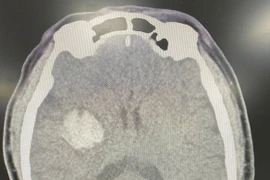

Bà Hà Thị T (56 tuổi, Thị trấn Yên Lập, Huyện Yên Lập, Phú Thọ) đang ăn cơm bỗng dưng đau đầu, mất ý thức và khi vào cấp cứu bác sĩ cho biết bà bị chảy máu não.

(khoahocdoisong.vn) - Tăng huyết áp là một yếu tố nguy cơ hàng đầu của đột quỵ chảy máu não. Tỷ lệ tăng huyết áp ở giai đoạn cấp đột quỵ chảy máu não chiếm khoảng 80% số bệnh nhân. Bệnh thường khởi phát đột ngột làm mất chức năng của não, gây tổn thương thần kinh khu trú: Liệt hoặc bại nửa người, liệt dây thần kinh số VII trung ương, có hoặc không có rối loạn cơ vòng, có hoặc không có rối loạn ngôn ngữ.